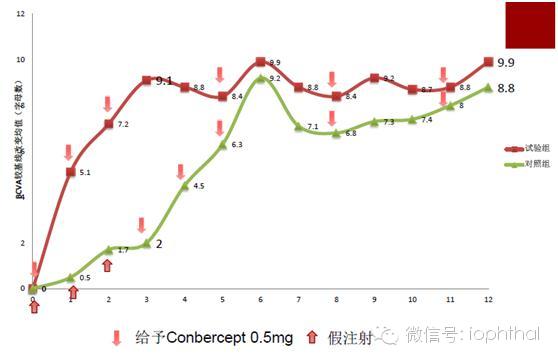

PHOENIX试验在延长期就采用了每3个月注射一次(Q3M)的方案,而患者视力改善能持续保持下去。核心期被分配到假注射组的患者在延长期头3个月接受康柏西普Q1M治疗后,视力提高程度也迅速追平了治疗组,在1年随访结束时,两组的有效性相似(图1)。

图1. PHOENIX试验中康柏西普显著提高患者视力